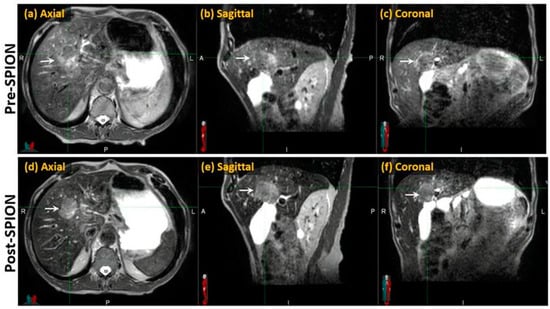

Compared to the pre-SPION image sets, SPIONs improved tumor visibility in the post-SPION images. The tumor boundary is clearly shown in the post-SPION images across all primary and metastatic liver tumors (Figure 3d–f), with negatively enhanced liver parenchyma.

Figure 3. Pre- and post-SPION MR images of HCC (arrows) in the first and second row, respectively.